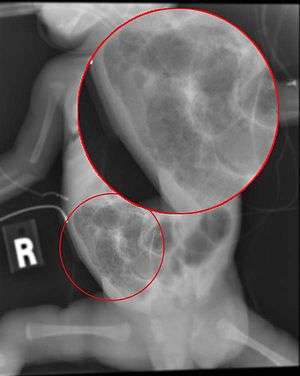

Radiograph of an infant with necrotizing enterocolitis | |

The diagnosis is usually suspected clinically but often requires the aid of diagnostic imaging modalities, most commonly radiography. Specific radiographic signs of NEC are associated with specific Bell's stages of the disease:[2]

- Specific radiologic signs (pneumatosis intestinalis or portal venous air)

- Severe radiologic signs (pneumoperitoneum)